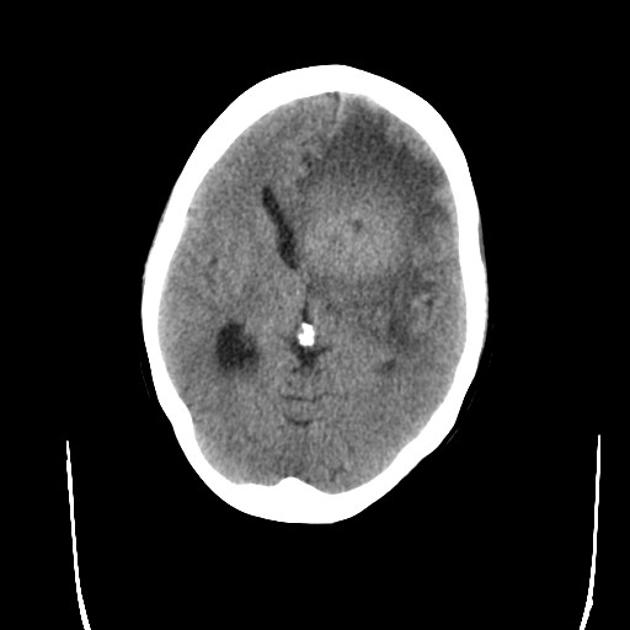

CT Imaging

CT images are hypointense. Hemorrhage is uncommon. Multiple lesions are more common in HIV+ patients.